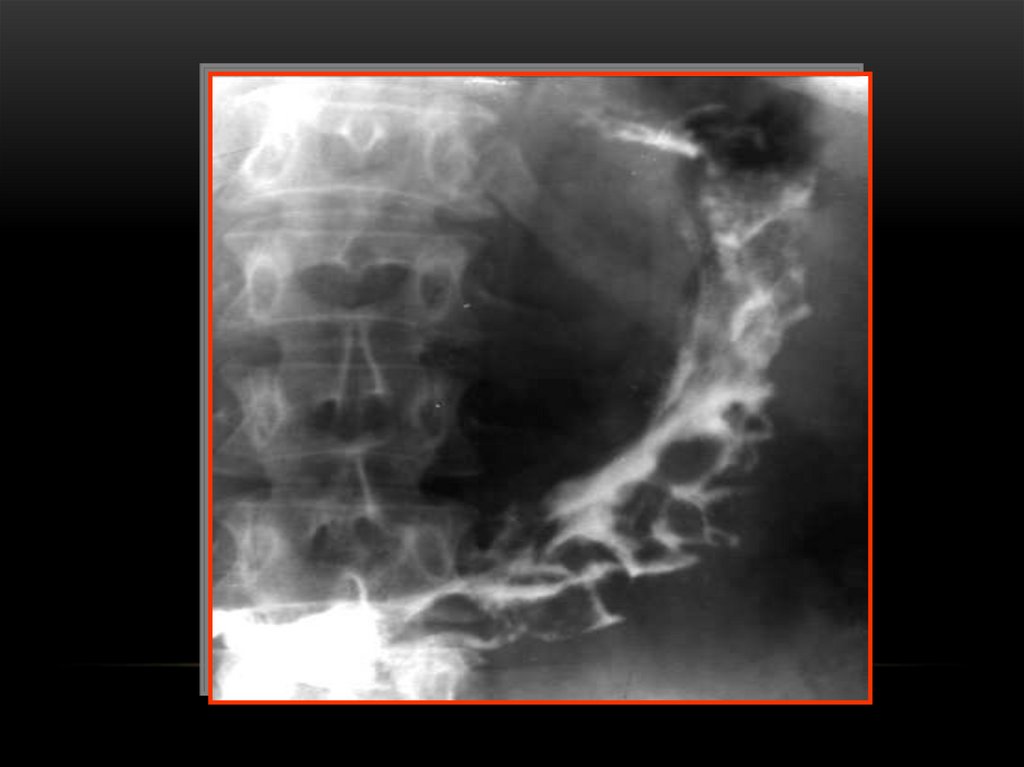

ГАСТРИТ

Асқазанның шырышты қабатының

қабынуы